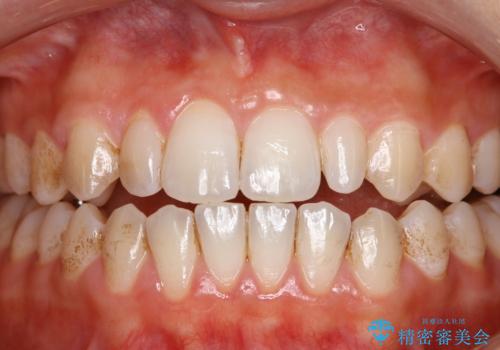

- 矯正中に歯の表面の掃除、歯を白くしたいとのことで来院されました。

PMTCとオフィスホワイトニングを行いました。

ステインが全体的についていたのでPMTCでステインを除去しオフィスホワイトニングを行いました。

ホワイトニングは薬剤を塗布し、レーザー照射を三回行いました。